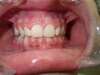

Classe 2

AVANT